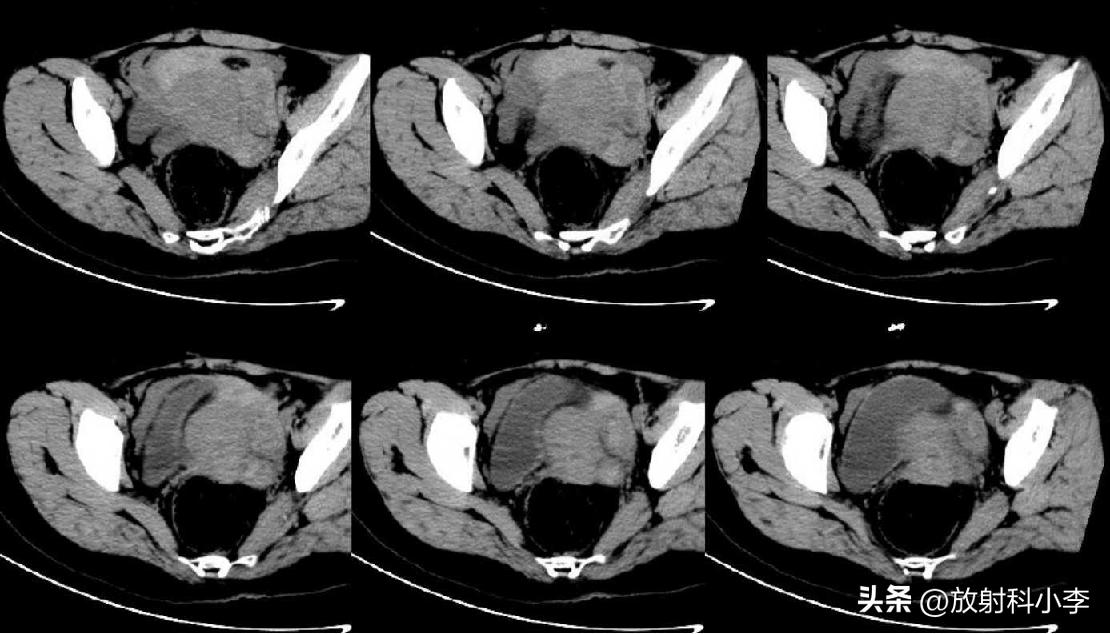

case 1. F,33Y,突发下腹痛1天

增强CT:左侧附件区囊性肿块(箭)与周围盆腔积血。H=盆腔积血,U=子宫。

术后诊断:左侧输卵管异位妊娠破裂

case 2. F,27Y,下腹痛2天,加剧5小时

妇科检查:宫颈举痛、摇摆痛;后穹窿穿刺4ml不凝血;

术前CT示:腹腔内出血,左侧附件区囊性灶,伴周围盆腔环状稍高密度影,???考虑异位妊娠可能?

术中:子宫前位,正常大小,左侧输卵管壶腹部破裂出血,清理出血块2000ml,积血块中见绒毛组织。

术后诊断:左侧卵巢妊娠破裂。